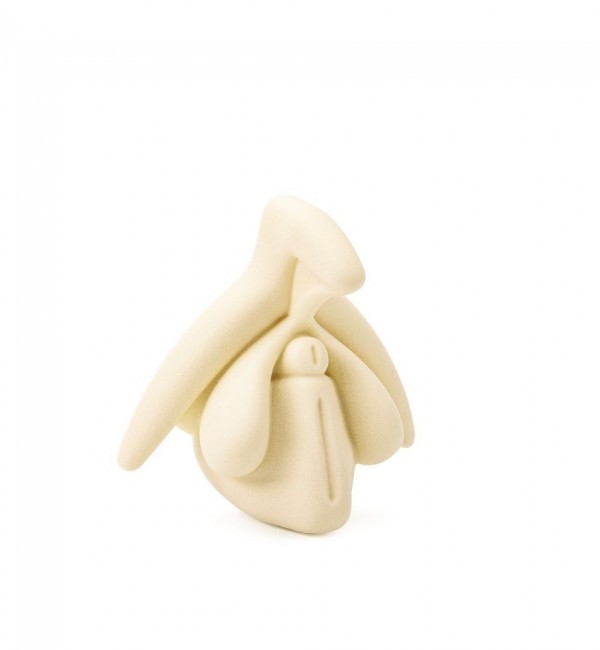

I dilatatori Vagiwell sono dispositivi medici per la dilatazione vaginale in silicone medico, pieni all’interno, in modo da garantire la sufficiente rigidità necessaria all’inserimento ma piacevoli al tatto.

Un’apertura concava ne facilita l’introduzione senza che sia necessario fare leva con un applicatore.

Le 5 misure (integrabili con la sesta, di diametro superiore) favoriscono l’esercitazione progressiva.

I diversi colori facilitano l’identificazione della misura in uso e sono dotati di un comodo astuccio in nylon per riporli.